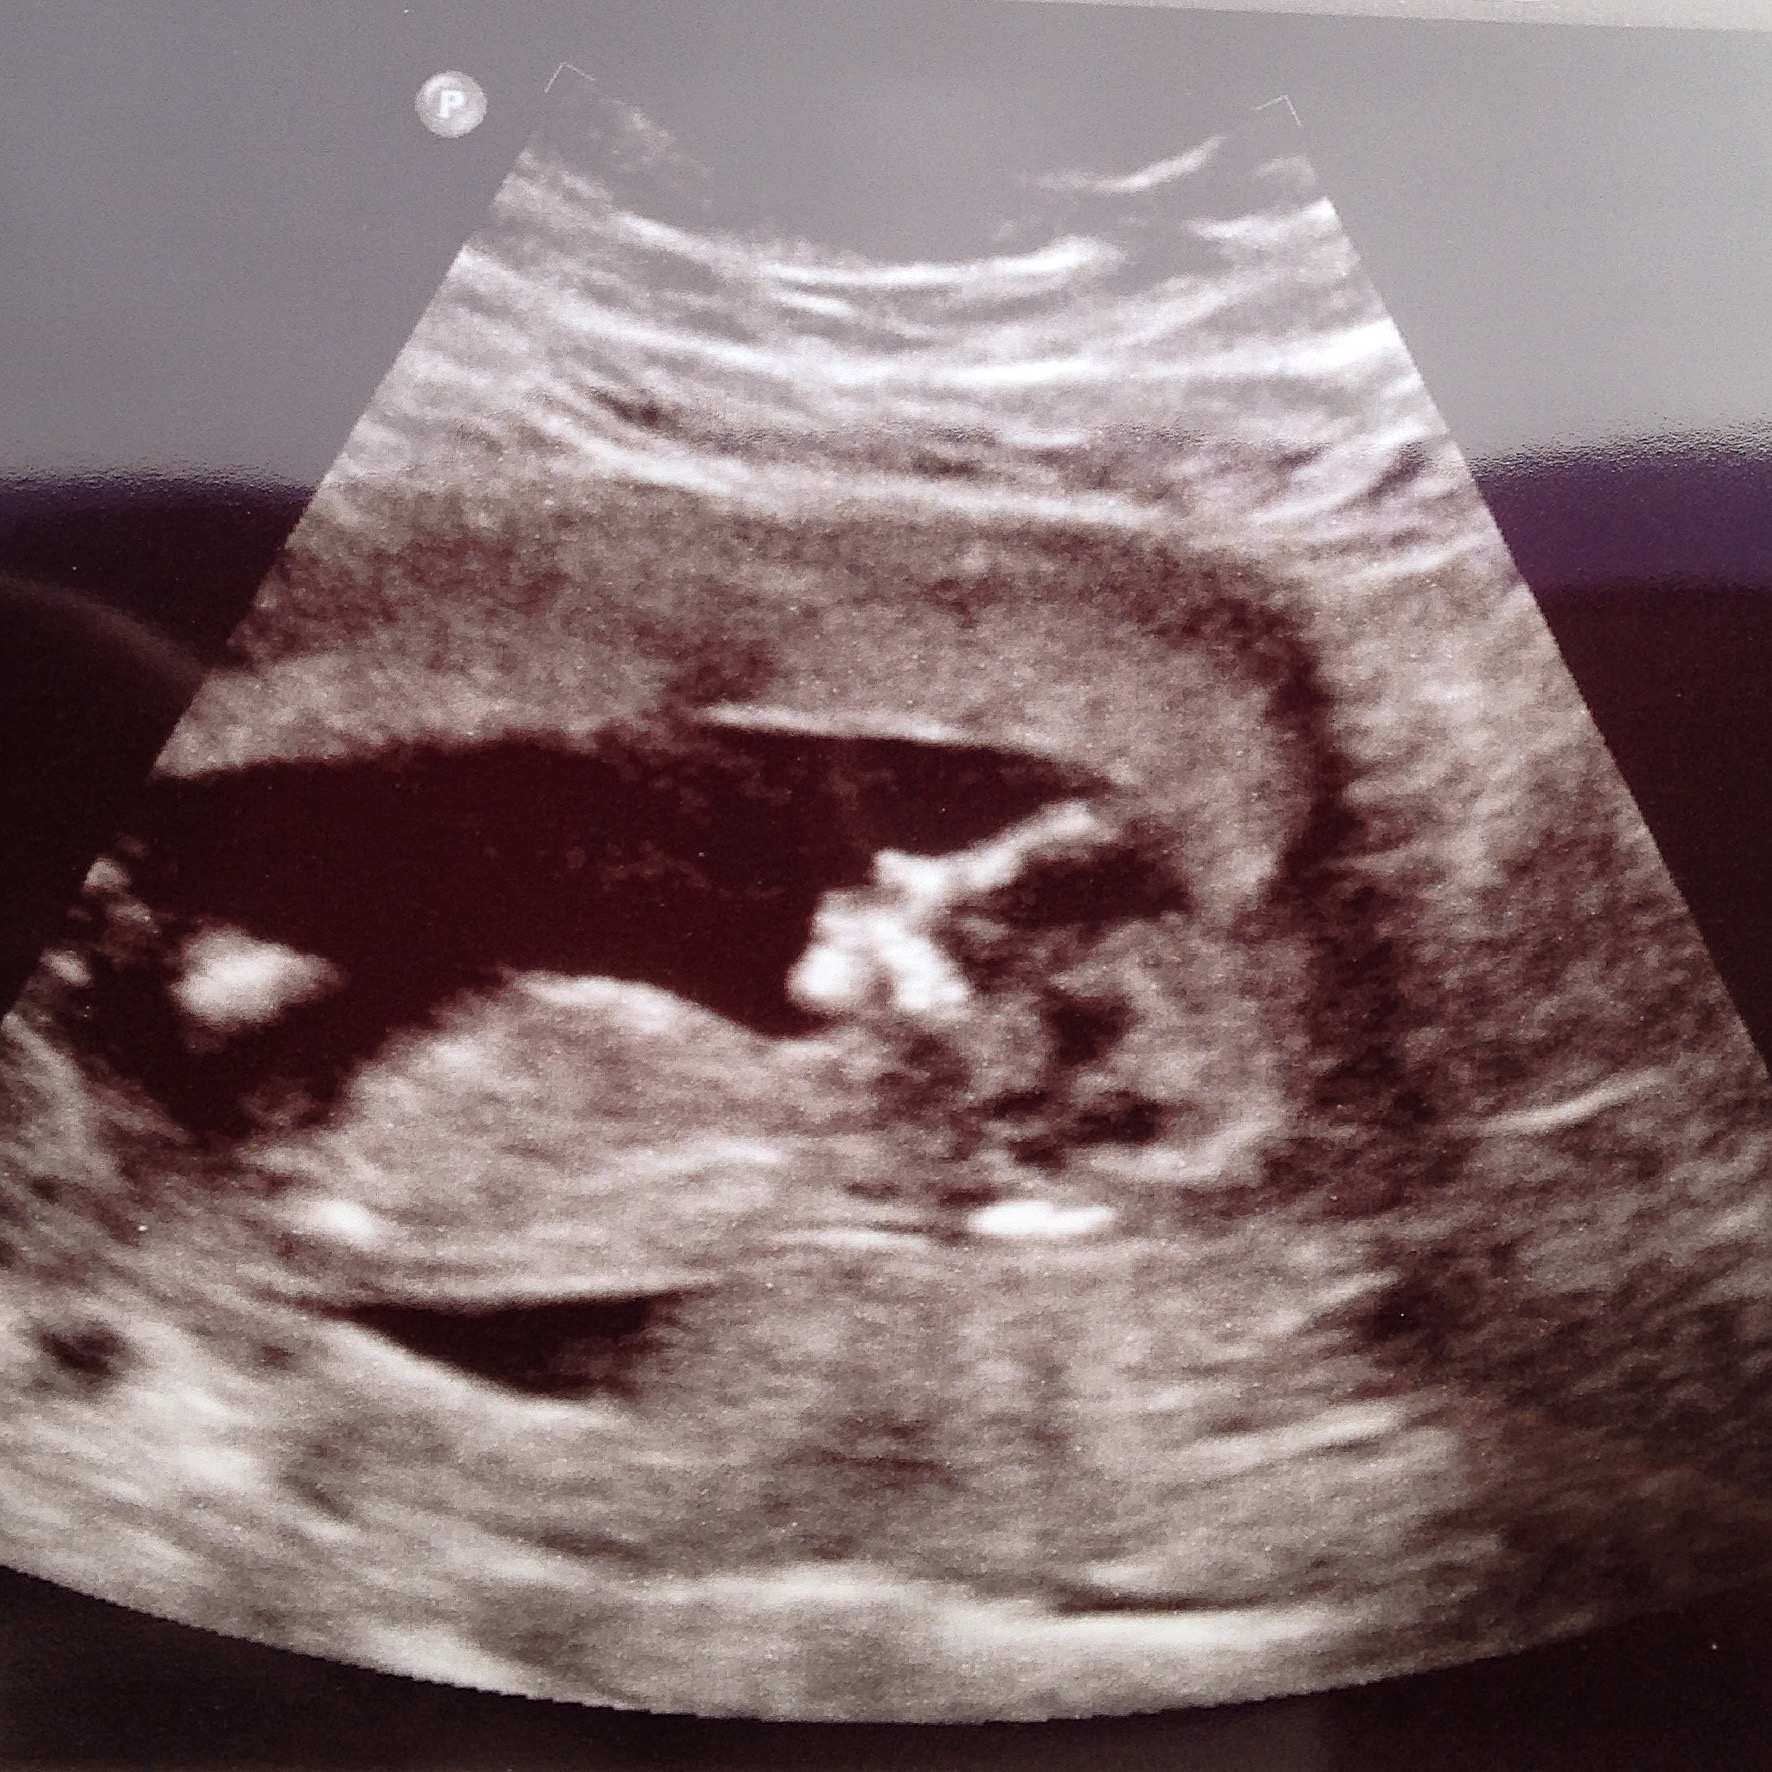

C'mon ladies, am I having a boy or girl? Attachment 22459

Nub area seems cut off a bit.

Boy flat forehead